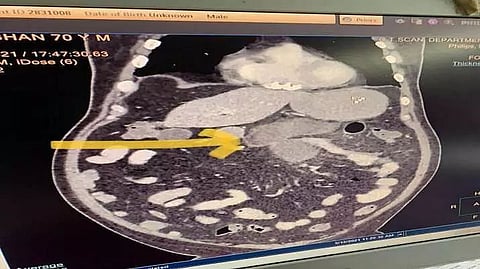

Both the patients, including one aged 68 years, are being treated at Delhi's Sir Ganga Ram Hospital for more than a week. "It is observed for the first time that the black fungus infected the lower intestine and even made a hole in it," said Ganga Ram Hospital authorities.

Kumar (name changed on request), a resident of Delhi, had barely completed the last rites of his wife when he experienced pain in his abdomen. He had been tested positive for COVID along with his wife and had been experiencing mild covid symptoms initially. (IANS)